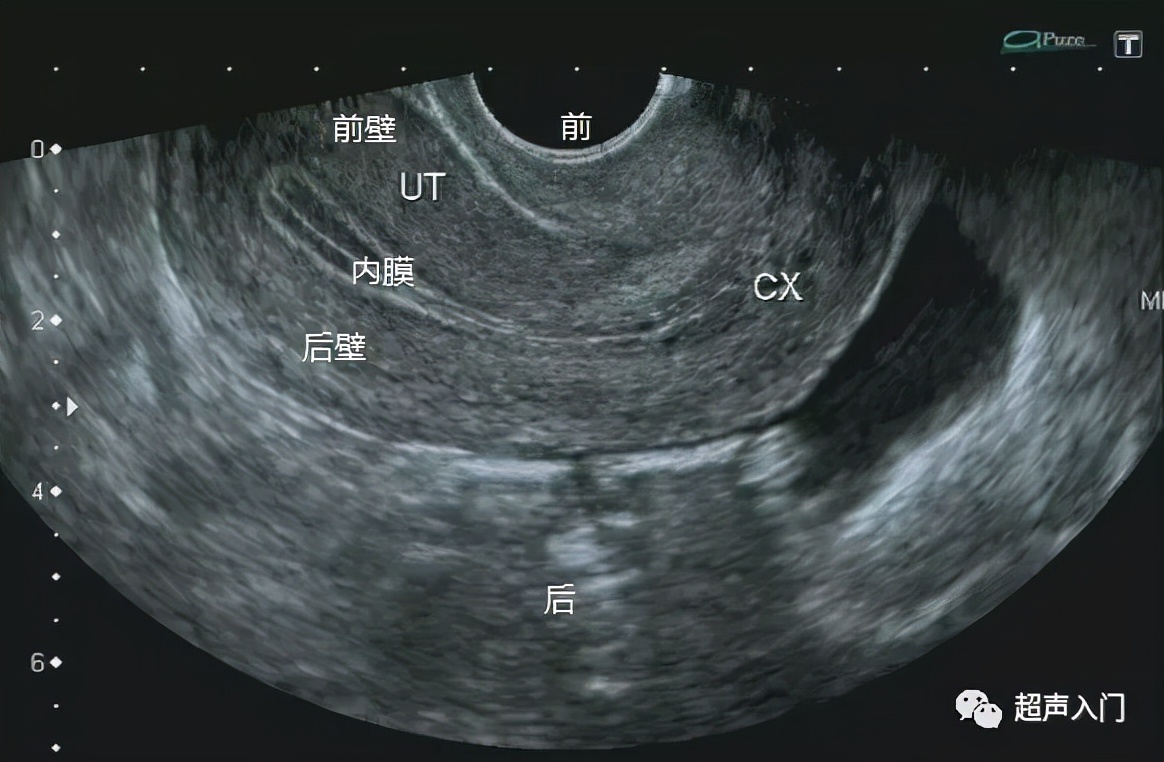

当经阴道超声矢状切子宫时,对应的图像就是下图这样的。

实际设备上的成像

当然,有的老师喜欢用反转后的图像,这个根据个人操作习惯来决定。但不管如何反转,始终是靠近腹侧的是前壁,靠近背侧的是后壁。